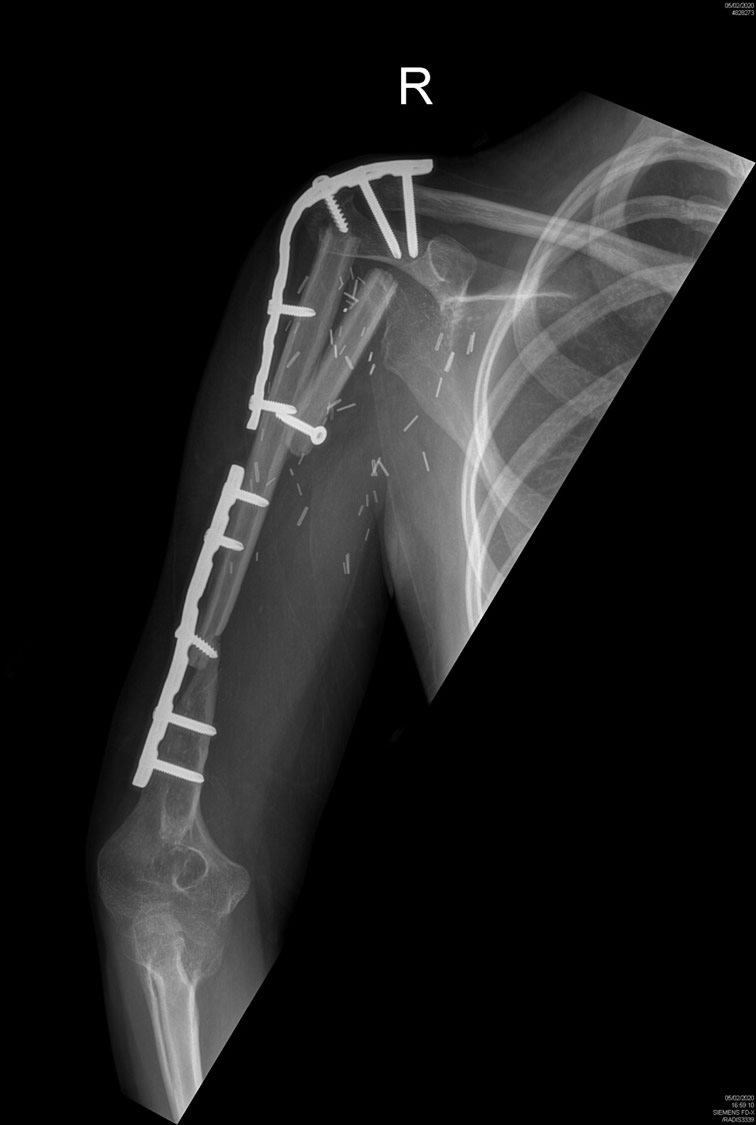

Defecto humeral masivo por prótesis oncológica infectada: reconstrucción con peroné microvascular

Paciente de 25 años que acude por defecto óseo masivo de húmero y hombro tras retirada de megaprótesis oncológica. La mano y el codo son funcionales pero el defecto óseo impide por completo cualquier función de la extremidad.

Paso 1: Reconstrucción de húmero y fusión de hombro

Se reconstruyó el húmero con colgajo microvascular de peroné tallado para optimizar la fusión del hombro.

Extremidad preservada. Miembro superior funcional.

- Extremidad preservada sin amputación

- Excelente función de mano, muñeca y codo y estabilidad de hombro

- Curación de la infección